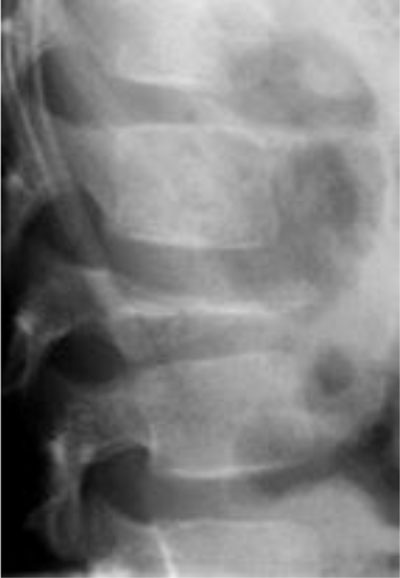

Figure 9

Eosinophilic granuloma (solitary form of Langerhans’ cell histiocytosis). Lateral radiograph shows collapse of the vertebral body L1 (vertebra plana).